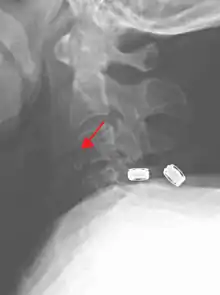

On CT scan or X-ray, a cervical fracture may be directly visualized. In addition, indirect signs of injury by the vertebral column are incongruities of the vertebral lines,[7] and/or increased thickness of the prevertebral space:[8]

X-ray of normal congruous vertebral lines